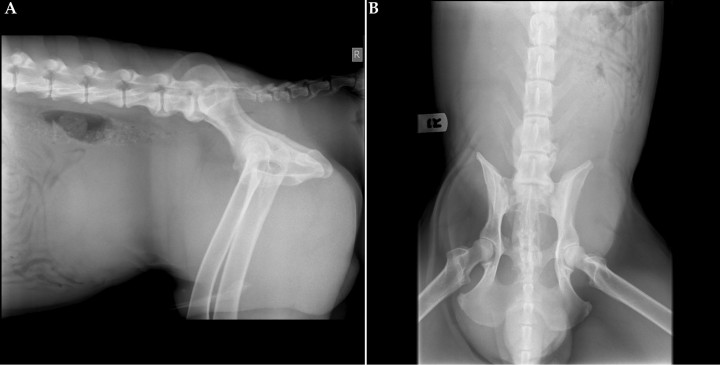

Se presentó en la consulta un perro de raza Weimaraner, macho no castrado de 3 años de edad, por una protrusión de la zona perineal izquierda, así como una historia de disuria y estreñimiento crónico desde hace una semana. En el examen físico se apreció distensión abdominal. Se hizo un estudio radiológico del abdomen, con proyecciones lateral derecha (Fig. 1A) y ventrodorsal (Fig. 1B).

<p>(<strong>A</strong>) Proyección lateral derecha. (<strong>B</strong>) Proyección ventrodorsal de abdomen de un perro de tres años de edad que se presenta con historia de disuria, estreñimiento y protusión perineal.</p>

Figura 1

(A) Proyección lateral derecha. (B) Proyección ventrodorsal de abdomen de un perro de tres años de edad que se presenta con historia de disuria, estreñimiento y protusión perineal.

Se visualiza una masa redondeada de opacidad tejido blando ocupando el abdomen caudal desde L4 a L7, además de pérdida de definición de serosas. Produce efecto masa con desplazamiento craneal y hacia el lado izquierdo de asas intestinales, así como desplazamiento dorsal del colon descendente, produciendo una estenosis de su luz a nivel de L7 que se continúa caudalmente hasta la primera vértebra coccígea (Fig. 2A y 2B). Además, se visualiza una estructura de opacidad tejido blando que se extiende desde abdomen caudal hacia el canal pélvico, protruyendo hacia la región perineal. Puede observarse también osteoartrosis a nivel de L6-S1 (Fig. 2A).

<p>Mismas imágenes que en Figura 1. (<strong>A</strong>) Proyección lateral derecha. Se observa una estructura de opacidad tejido blando ocupando el abdomen caudal (asterisco), con desplazamiento craneal de las asas intestinales (flecha negra) y desplazamiento dorsal del colon descendente, produciendo estenosis de su luz a nivel de L7 (flecha blanca). (<strong>B</strong>) Proyección ventrodorsal. Al igual que en la proyección lateral, se observa la misma estructura de opacidad tejido blando (asterisco), así como el desplazamiento de las asas intestinales (flechas negras).</p>

Figura 2

Mismas imágenes que en Figura 1. (A) Proyección lateral derecha. Se observa una estructura de opacidad tejido blando ocupando el abdomen caudal (asterisco), con desplazamiento craneal de las asas intestinales (flecha negra) y desplazamiento dorsal del colon descendente, produciendo estenosis de su luz a nivel de L7 (flecha blanca). (B) Proyección ventrodorsal. Al igual que en la proyección lateral, se observa la misma estructura de opacidad tejido blando (asterisco), así como el desplazamiento de las asas intestinales (flechas negras).